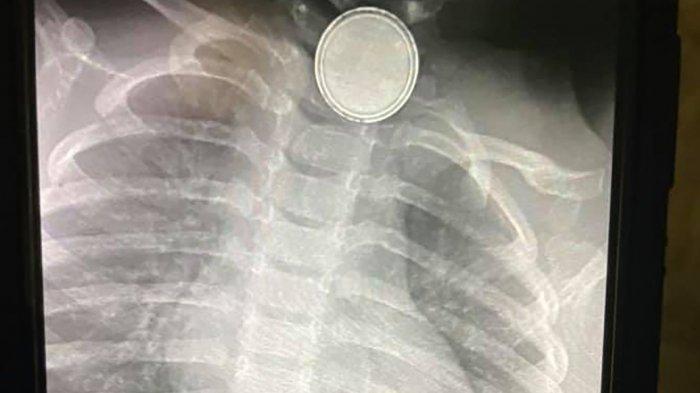

Setelah dilakukan rontgen, dokter memastikan bahwa bayinya menelan baterai remot itu.

Baterai tersebut menyangkut di kerongkongan bayi itu dan mengakibatkan 2 lubang pada kerongkongannya.

Menurut keterangan ibu korban, ada 2 lubang yang terdapat pada kerongkongan korban.